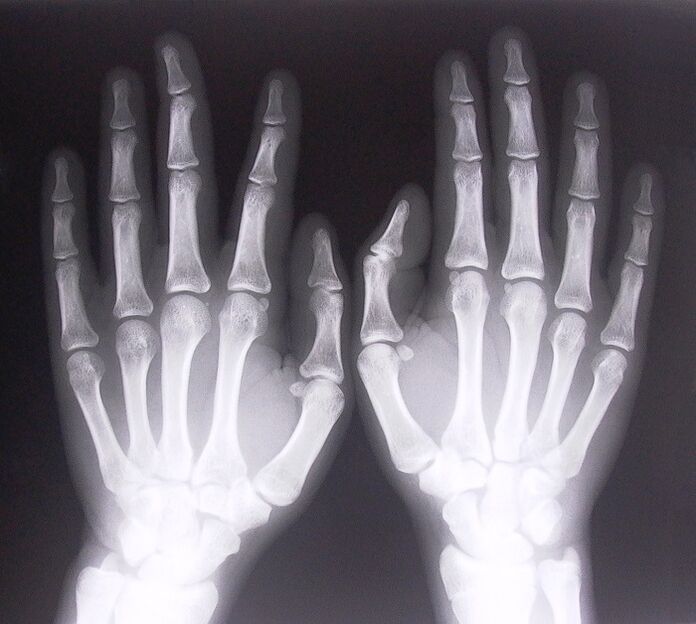

- stenosing ligamentitis.To identify the cause of the disease, it is necessary to undergo X-ray.Symptoms are typical: painful shaking of the hand, rotation of the clenched palm.Also, during extension, clicks are usually heard.

To start treating joint pain in the fingers, you need to correctly determine what disease caused them.To determine what type of disease a person is suffering from who feels pain in the joints when turning the arm, doctors recommend undergoing the following procedures:

- Take an X-ray.